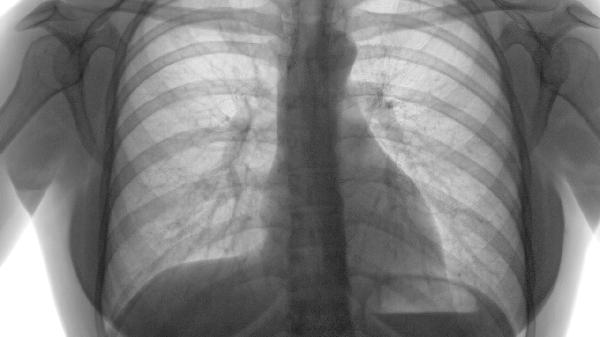

肺气肿患者气喘发作时可遵医嘱使用布地奈德福莫特罗粉吸入剂、沙美特罗替卡松粉吸入剂、氨茶碱片、多索茶碱片、噻托溴铵粉雾剂等药物控制症状。肺气肿是慢性阻塞性肺疾病的主要表现,需长期规范用药以延缓病情进展。

肺气肿患者除规范用药外,应严格戒烟并避免接触粉尘等刺激物,坚持腹式呼吸训练可改善肺功能。冬季注意保暖防感冒,接种流感疫苗和肺炎疫苗有助于预防急性加重。日常饮食宜高蛋白、高维生素,适量有氧运动如散步、太极拳可增强呼吸肌耐力。定期复查肺功能,出现气促加重、痰量增多时应及时就医调整治疗方案。